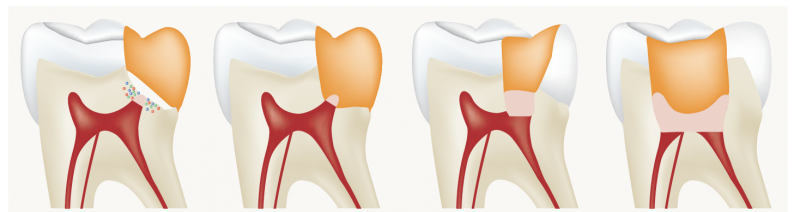

L’endodontie est le domaine de l’odontologie qui consiste en la prévention, le diagnostic et le traitement des maladies de la pulpe dentaire et des maladies péri-apicales et péri-radiculaires associées (l’apex de la dent étant le bout de la racine, par où entrent les vaisseaux sanguins et les nerfs de la pulpe dentaire).

L’endodonte (l’intérieur de la dent) constitue une voie de passage des bactéries vers l’intérieur de l’organisme. Le but du traitement endodontique est donc de fermer cette voie de passage lorsqu’elle a été ouverte par une lésion (carie, traumatisme).

Les différents traitements endodontiques sont les coiffages pulpaires directs ou indirects, la pulpotomie, la pulpectomie, l’obturation a retro (chirurgie endodontique) ainsi que les techniques de régénération.